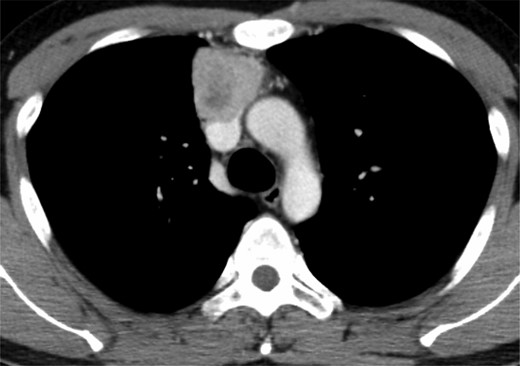

A 33-year-old man was referred to our hospital because of abnormal chest shadow. Contrast-enhanced computed tomography (CT) revealed a 50-mm-diameter mass in the anterior mediastinum (Fig. 1). Invasion of the anterior wall of the SVC was suggested because of the unclear border between the tumor and the SVC. 18F-Fluorodeoxyglucose uptake on positron emission tomography exhibited a maximum standardized uptake value of 6.5. From radiographic findings, the mass was suspected to be a malignant tumor such as a thymoma or thymic cancer, although a pathological diagnosis was not established. Therefore, we planned extirpation of the tumor via a median sternotomy.

Contrast-enhanced CT showing an anterior mediastinal tumor with suspected invasion of the SVC.